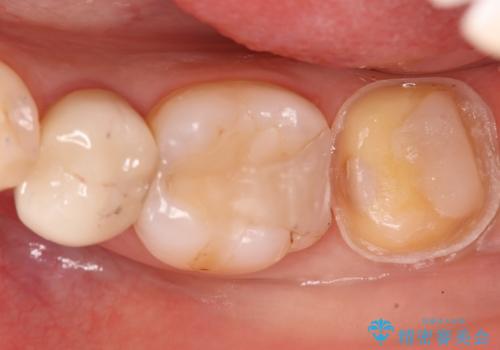

- 奥歯に虫歯があると言われて治療された患者様です。

何度か同じ歯に保険治療で治したそうですが、欠けたり再度う蝕になってしまった経験から自費治療を希望され、丈夫でキレイなセラミッククラウンにて治療いたしました。